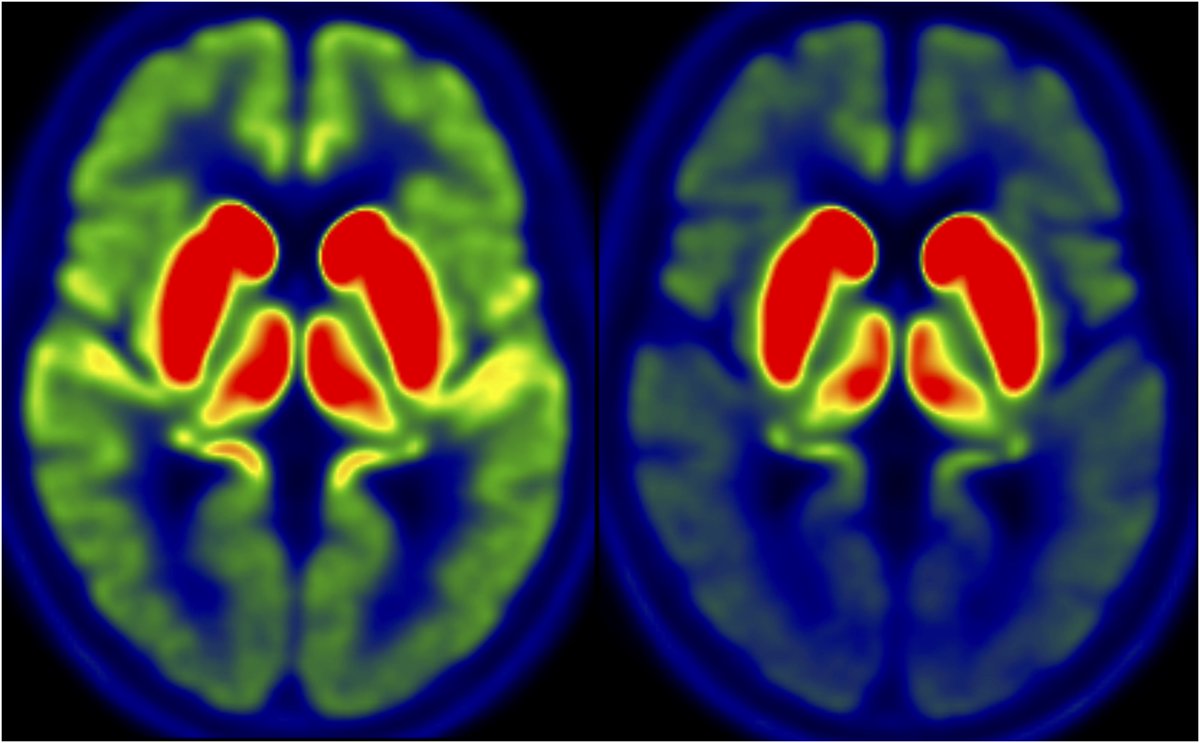

Aarhus University researcher with hunch for neurodegenerative diseases and alpha-synuclein

Our MJFR14-PLA (bioRxiv 2024.07.08.602186) demonstrates early and pervasive non-inclusion a-syn aggregate pathology in synucleinopathies corroborating previous PLA studies DANDRITE, Aarhus University, michaeljfox.org, Lundbeckfonden, @alpha_synuclein